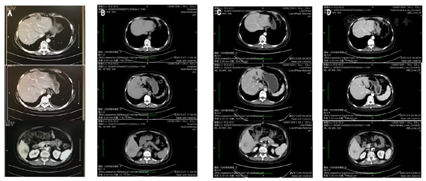

2019年8月6日,患者于内分泌治疗6个月时复查,腹部B超发现:肝内多发实性占位,较大一处3.2 cm×2.5 cm。肝脏CT检查结果一致(图2)。行穿刺病理活检(2019年8月20日)提示:肝脏查见异型细胞巢,形态结合病史符合乳腺癌肝转移。免疫组化提示:GATA-3(+),ER(1+,中等强度,15%),PR(1+,中等强度,50%),Her2(2+),Fish(-),Ki67(约30%)。于2019年9月14日复查肝脏转移灶/外周血ctDNA检测,提示基因突变特征与基线时一致(图1)。患者乳腺癌肝脏转移诊断明确。

参考CSCO乳腺癌诊治指南,我们推荐患者接受氟维斯群联合CDK4/6抑制剂治疗,但是患者表示经济困难,选择化疗治疗。2019年8月至2020年1月,患者接受了一线解救化疗(白蛋白结合紫杉醇200 mg单周方案)共14次,疗效评价PR。期间行肝脏CT检查,疗效评估SD(Stable Disease)。复查外周血ctDNA检测,PIK3CA等基因的变异率明显下降,疗效评估PR(图1,2019年10月20日,2019年11月29日)。因为疫情,患者1个月余未能继续治疗。2020年2月27日,复查肝脏CT检查时,提示肝脏转移灶增大,且左侧胸壁出现赘生物,局部破溃。临床评估为PD。2020年3月至8月,患者接受二线解救化疗(长春瑞滨50mg 2周方案联合盐酸安罗替尼12mg 3周方案)治疗,复查肝脏CT提示转移灶稳定(图2),复查外周血ctDNA检测,提示变异率下降,疗效评估为PR(图1,2020年4月11日,2020年7月20日)。2020年8月底,患者决定转至外院治疗,又经历了3线治疗,每次治疗的缓解期2~3个月。2021年6月2日,患者再次行外周血ctDNA检测,提示突变率又有所提高,提示病情可能再次进展(图1,2021年6月2日)。此时患者的肝脏CT检查提示病情稳定,且患者并无任何不适,外院医生参考主诉及影像学检查结果,讨论后建议维持原方案治疗。2021年8月11日,患者出现乏力、腹胀等症状,复查外周血ctDNA检查发现,变异率等指标明显升高,例如PIK3CA突变率达35.92%,TP53突变率达35.44%,接近肝脏转移灶组织的变异水平(图1,2021年8月11日),提示癌细胞生长迅速,病情爆发式进展。此时,患者病情急转直下,于8月18日去世。具体治疗过程可见图3。